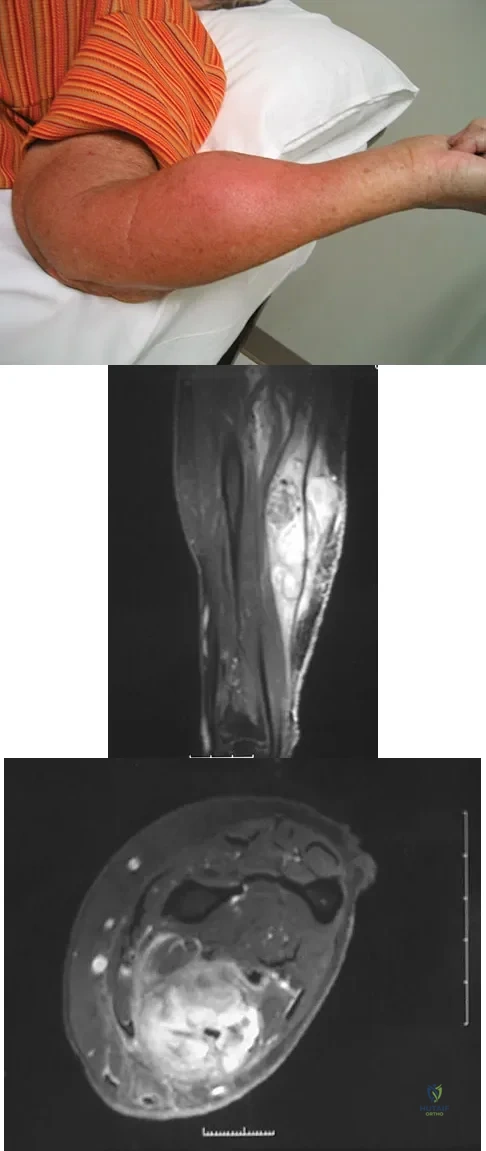

A 7-year-old girl has had a painful forearm for the past 2 months. Examination reveals fullness on the volar aspect of the forearm. Radiographs and an MRI scan are shown in Figures 42a through 42c. Biopsy specimens are shown in Figures 42d and 42e. What is the most likely diagnosis?

Figure 8a shows the clinical photograph of an 83-year-old woman who has an enlarging left forearm mass. MRI scans are shown in Figures 8b and 8c. What is the next most appropriate step in management?